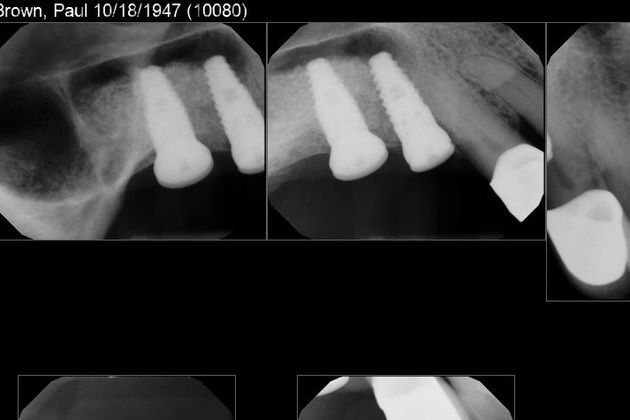

Patients moving to Austin often need a restorative dentist to complete their case started prior to them moving here. This was a pair of BioHorizon dental implants in the patient's upper right quadrant. The patient moved from Chicago to Austin this year and needed help restoring his newly placed implants. We were easily able to fabricate two custom dental crowns that were delivered effortlessly and painlessly in a short appointment.